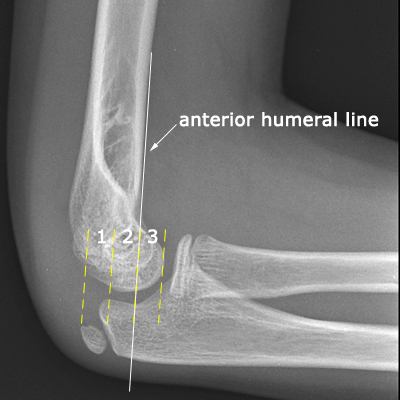

humeral line anterior elbow supracondylar pediatric fractures normal radiology fracture humerus radiopaedia capitellum angle capitulum joint case types injuries occult

elbow ray radial fracture head normal alignment line anterior humeral coreem

elbow forearm normal lateral alignment anterior capitellum radiograph interpreting radiographs fracture supracondylar intersect

elbow line anterior normal radiocapitellar humeral fractures adults lateral radiograph dislocations imaging

humeral radiocapitellar elbow radiographic

elbow humeral fracture supracondylar forearm capitellum radiographs interpreting intersect

elbow xrays humeral radiocapitellar emdocs fracture

elbow xrays anterior humeral radiocapitellar emdocs fracture

radiopaedia line humeral anterior radiology

capitellum dislocation elbow pediatric through drawn lateral anterior humeral pass should line

Anterior humeral line. Pediatric humeral fracture. Elbow injuries